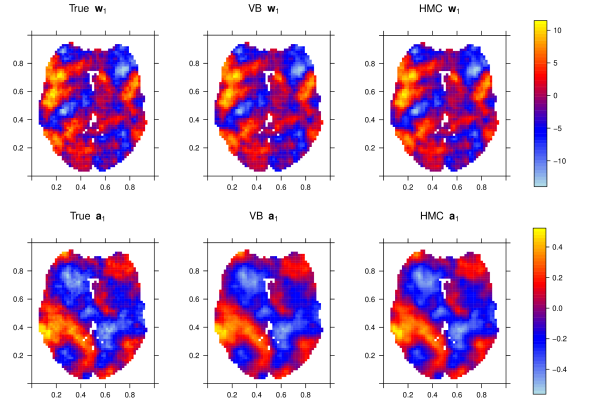

Both VB and HMC are applied to the simulated datasets and images depicting the average (over simulation replicates) posterior mean estimates obtained from both methods and the true values are shown in Figure 2, where we show the images corresponding to and . Figures depicting comparisons for the full set of parameters are shown in Figures 1-2 of the Supplementary Material. In this case the results obtained from HMC and VB are very similar and both correspond well with the truth.

Figure 3 shows the image of the average (over simulation replicates) posterior mean estimates from HMC and VB for and . Similar Figures for the remaining parameters are shown in the Supplementary Material, Figures 3-8. Both HMC and VB appear to provide similar estimates which correspond well with the truth.

Examining the results a difference is observed in the average (over simulation replicates) of the posterior mean, depicted in Figure 4. The estimates of the regression coefficients obtained from HMC appear to be smoother overall, and also tend to have larger bias when compared with those obtained from VB, while the two algorithms tend to give fairly similar results for the auto-regressive coefficients. A comparison of the numerical metrics is presented in Table 3, and this comparison shows that VB actually over-estimates the posterior variability relative to HMC. The Bayes estimates obtained from VB actually have smaller bias, but the MSE obtained from HMC is considerably lower, in particular for the first four regression parameters. Here we see an example where VB results in a poor approximation to the posterior. Interestingly, the posterior variability is actually over-estimated rather than under-estimated as is typical. This demonstrates that when VB misses the mark it is not necessarily going to under-estimate posterior variability.

Images depicting the estimated coefficients are shown in Figures 6 and 7. Due to space restrictions we only display the estimates of and on the plane out of planes along the z-axis. Additional figures displaying estimates for the other regression coefficients are presented in the Supplementary Material, Figures 13-14. As seen in the simulation studies, HMC and VB yield very similar posterior mean estimates in terms of auto-regressive coefficients. In terms of the regression coefficients, the estimates from HMC seem to be a bit smoother than those from VB, but still similar in general. Estimates from MUA seem to exhibit a greater degree of spatial smoothing.